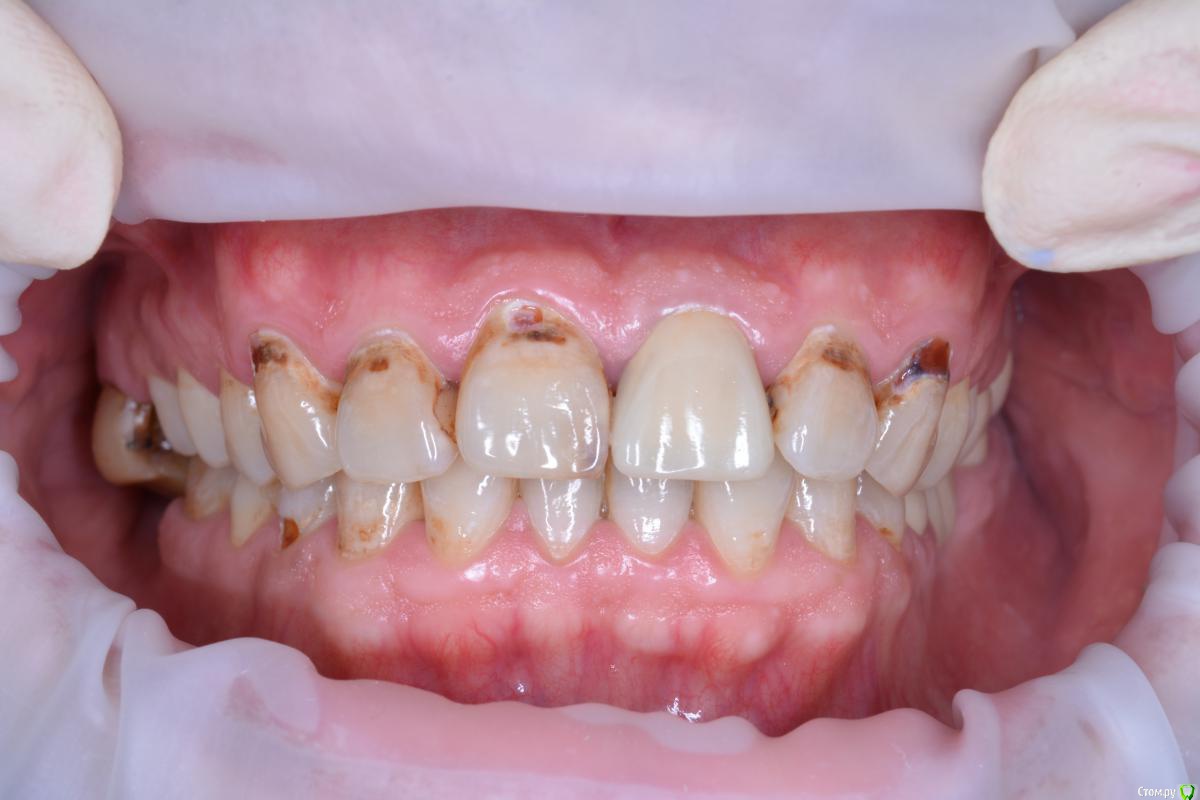

alekcandr ovs. Опубликовано 3 июля, 2017 Поделиться Опубликовано 3 июля, 2017 Планируется протезирование от 13---23 Получиться ли перекрыть цвет E.max??? может диоксид с нанесением??? Ссылка на комментарий

DmitrySH Опубликовано 3 июля, 2017 Поделиться Опубликовано 3 июля, 2017 Е.мах, кариес сперва полечите только. 1 Ссылка на комментарий

DR.P Опубликовано 3 июля, 2017 Поделиться Опубликовано 3 июля, 2017 (изменено) Сейчас, выполняю похожее лечение. Пролечил кариес этих флюорозных эрозий. Оттенок в тон культей. Все делал с коффердамом, получается ретракция платком и полное обнажение границ эрозий. Получилось отлично. После уже препарирование. Я выбрал виниры на рефракторе...но это потому что люблю его больше. Но так же можно сделать и на имаксе, думаю MO будет достаточно Изменено 3 июля, 2017 пользователем DR.P Ссылка на комментарий